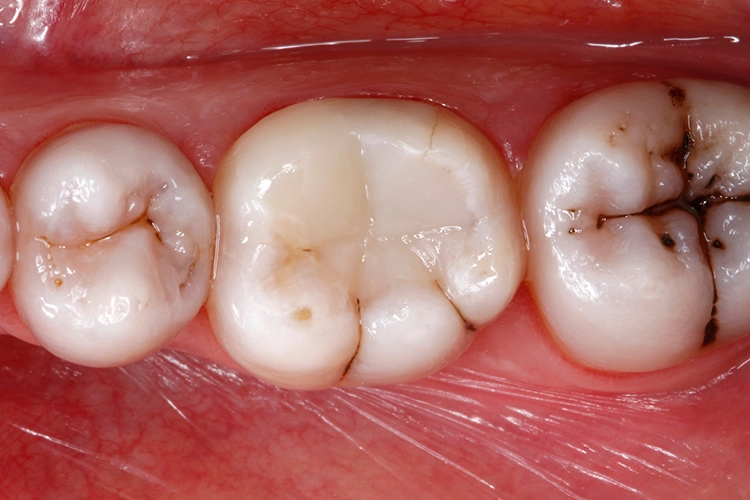

Anschließend wurden sämtliche Kavitätenränder mit einem Feinkorndiamanten nachgearbeitet und finiert. Danach wurden die pulpanahen Kavitätenareale mit einem selbstlimitierenden Polymer-Rosenbohrer (Polybur, Gebr. Brasseler GmbH & Co. KG, Lemgo) substanzschonend exkaviert (Abb. 7), eine Exposition der Pulpa konnte mit diesem Vorgehen der selektiven Exkavation vermieden werden (Abb. 8) [51–55]. Das pulpanahe Dentin im Zentrum der Kavität wurde mit einer dünnen Schicht röntgenopaker Calciumhydroxidpaste auf wässriger Basis (Calcicur, VOCO) indirekt überkappt (Abb. 9). Das Calciumhydroxidpräparat wurde mit einer partiellen Unterfüllung aus lichthärtendem kunststoffmodifiziertem Glasionomerzement (Ionoseal, VOCO) abgedeckt (Abb. 10).